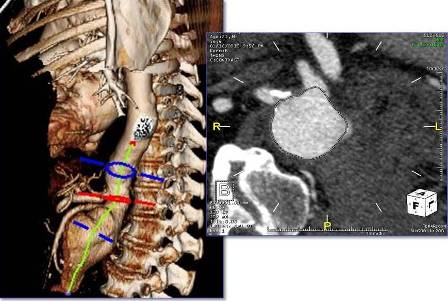

Using the most advanced, three-dimensional reconstruction

software, a custom-made endograft is planned and designed

for your patient’s specific anatomy.

Examples of Some of Our Recent Cases

About Fenestrated and Branched Endografts

For complex aneurysms (those aneurysms which include portions of the aorta with branch arteries that supply organs such as the kidneys and intestines), a special type of repair is required to preserve flow to these branch arteries: a fenestrated endograft, with special holes placed in the endograft at the precise location in which these branches arise. The fenestrated endograft is designed specifically to fit each patient’s particular anatomy; this is possible through the use of sophisticated imaging software that allows Dr Schanzer and his team to manipulate the CT images obtained of the patient’s aorta and branch arteries.

The fenestrated endograft, designed specifically for the particular patient, is then positioned inside the aorta from within the blood vessels in the groin; this allows for the aorta to be “re-lined”, with the holes positioned precisely to allow blood to continue to flow into the branch arteries, while blood flow no longer fills the aneurysm sac.